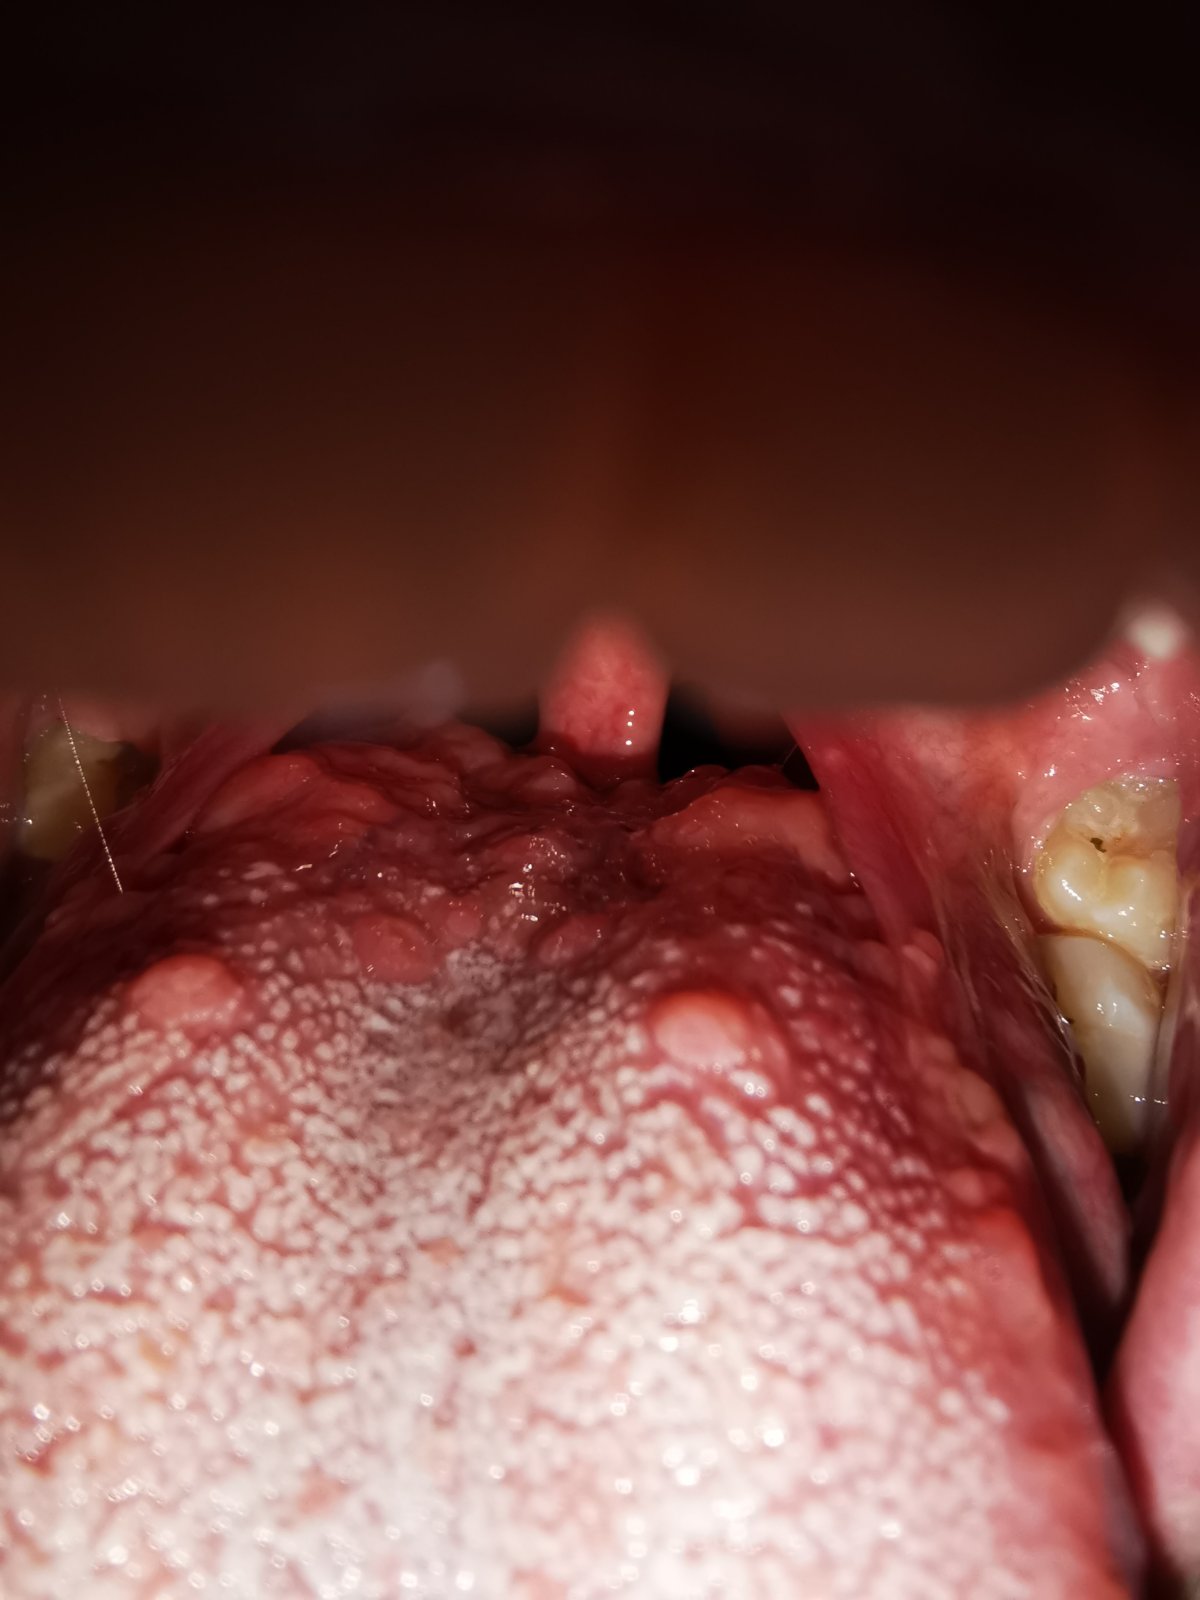

chcela by som sa poradiť ohľadom môjho problému. Vzadu ako je koniec jazyka mám pri koreni hrbolčeky. Žiadne ťažkosti nemám.

Je to v poriadku?

takéto hrbolčeky na jazyku má každý z nás. Ide o fyziologickú anatómiu jazyka.